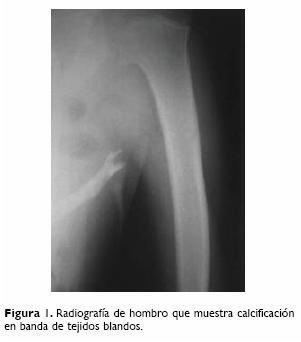

Caso 1. Niña de 12 años de edad, quien acudió por primera vez a esta institución a los ocho años, por un padecimiento de dos años de evolución, caracterizado por escoliosis toracolumbar y acortamiento de ambos pulgares, así como de los primeros ortejos, asociado a sensación de endurecimiento de tejidos blandos. Las deformaciones fueron corroboradas en la exploración física por medio de palpación de las mismas en región lateral derecha de cuello, cara anterosuperior derecha de tórax, en región de columna toracolumbar y en la cara anterior de ambos brazos; por este motivo se sospechó miositis osificante progresiva. En las radiografías de cuello, tórax, columna toracolumbar y extremidades superiores (Fig. 1) e inferiores se evidenciaron las calcificaciones en tejidos blandos. En el momento del diagnóstico se reportaron los siguientes exámenes de laboratorio: calcio 9.0 mg/dL, fósforo 4.3 mg/dL y fosfatasa alcalina 278 UI. Inició tratamiento con ácido retinoico durante un año y medio y rehabilitación con respuesta parcial, por este motivo se cambió a isotretinoína, con la cual fue manejada durante un año sin respuesta. Se suspendió este último fármaco y se inició tratamiento con prednisona 1.0 mg/kg/día durante cuatro semanas, sin mejoría. Entonces se decidió administrar metilprednisolona intravenosa a dosis de 30 mg por kg de peso cada 24 horas en tres ocasiones, y posteriormente con aplicaciones mensuales. En el momento en que se comenzó a administrar este medicamento, la paciente tenía una clase funcional III (era capaz de realizar actividades de autocuidado, tales como el baño, alimentarse, etc., pero las actividades escolares y de recreo se encontraban limitadas), dada principalmente por contracturas en flexión de cuello, codos, columna toracolumbar y rodillas.